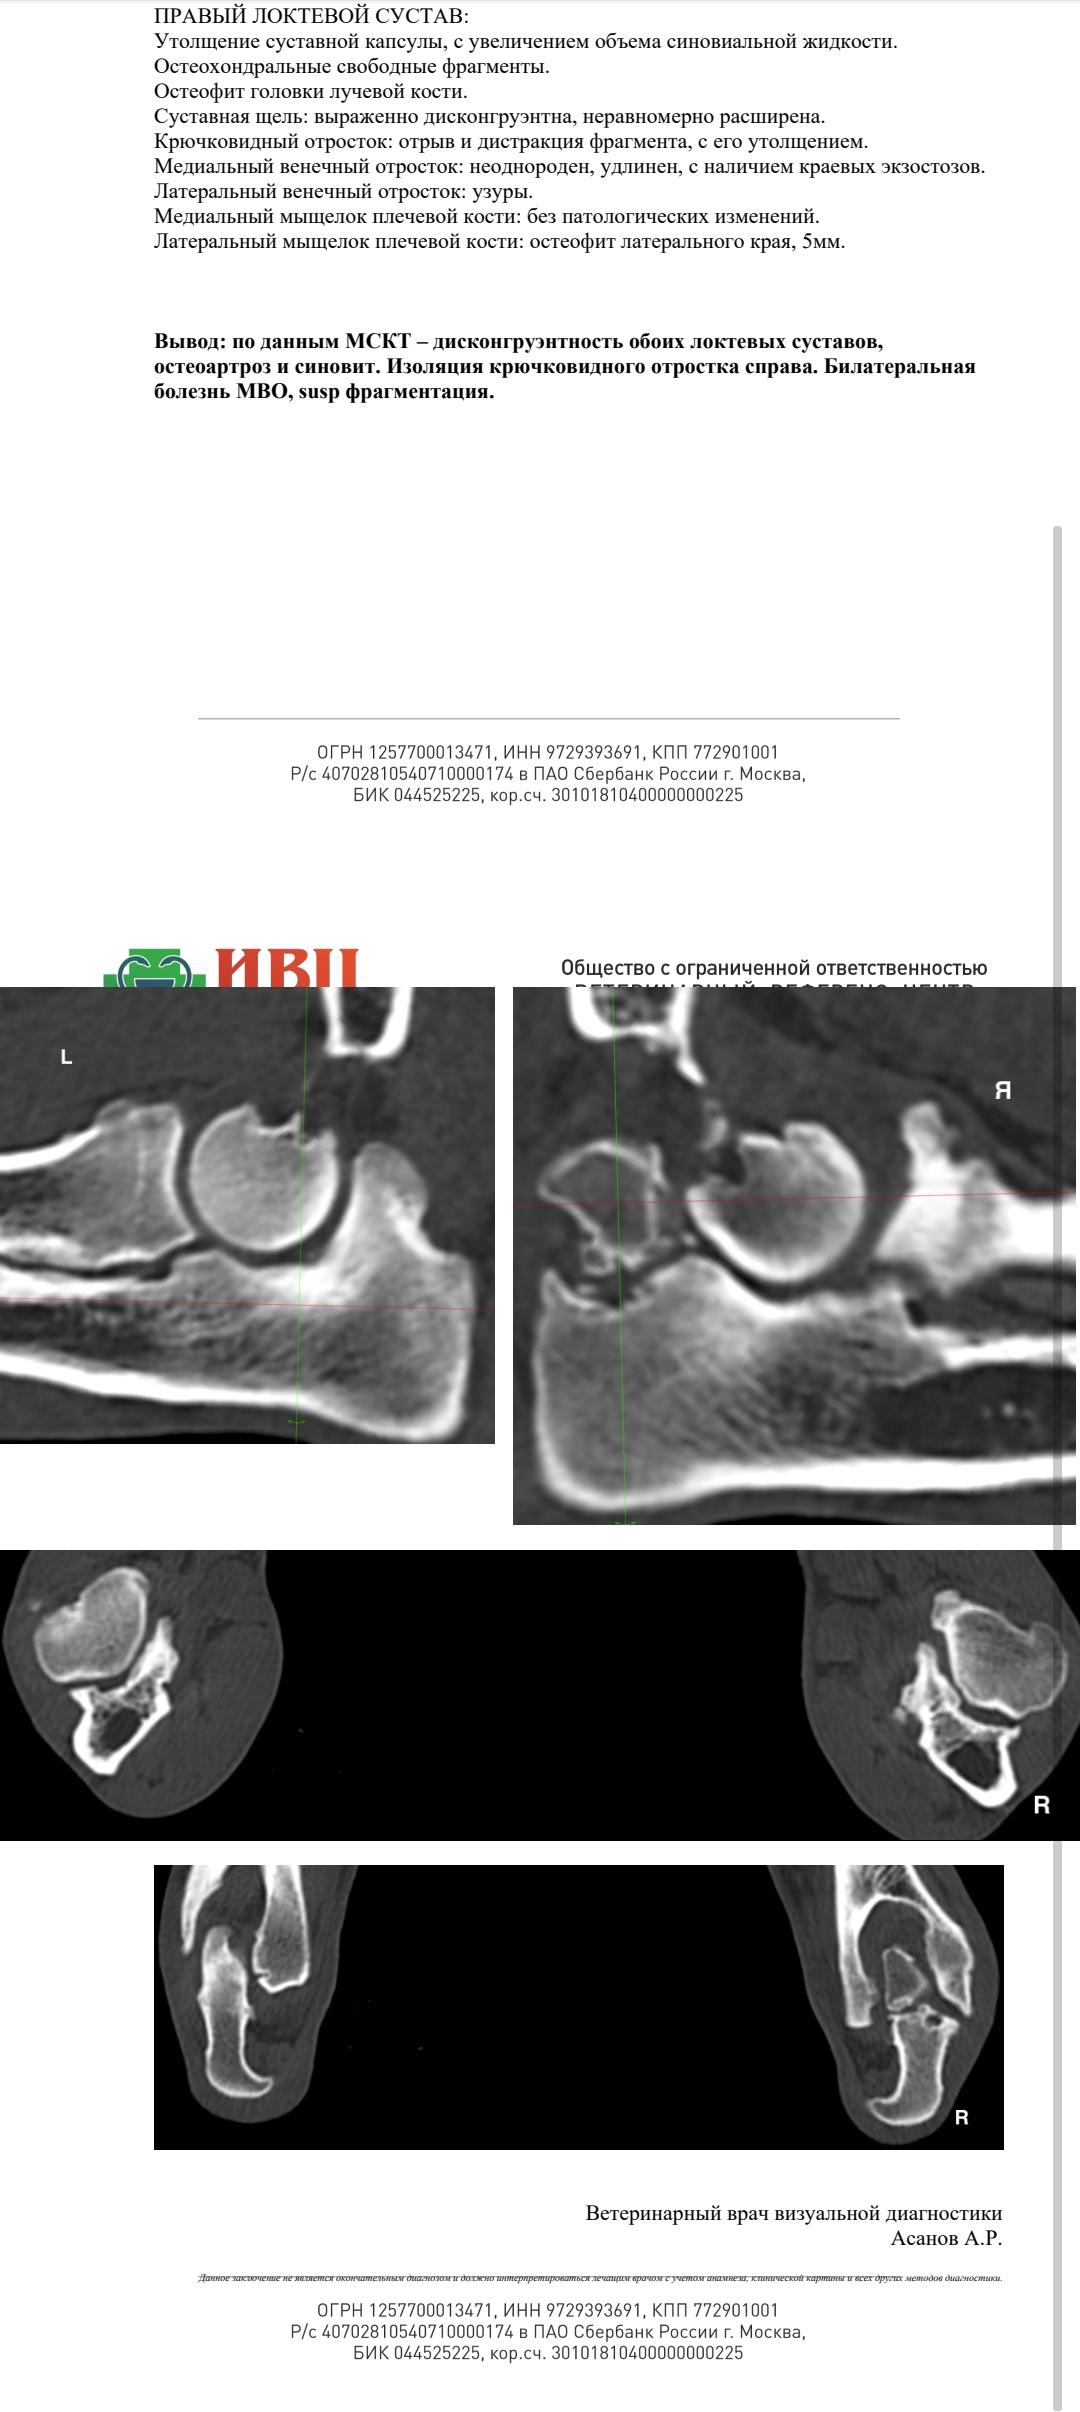

Результаты

От Александра Зотова:

[01.10, 14:07] Александр Зотов: Там остеотомия вне сустава по-любому.

Из сустава надо вытаскивать крючковидный и подчищать разростания

[01.10, 14:09] Александр Зотов: По деньгам если артротомия, крючковидный и остеотомия - около 60 выйдет наверное